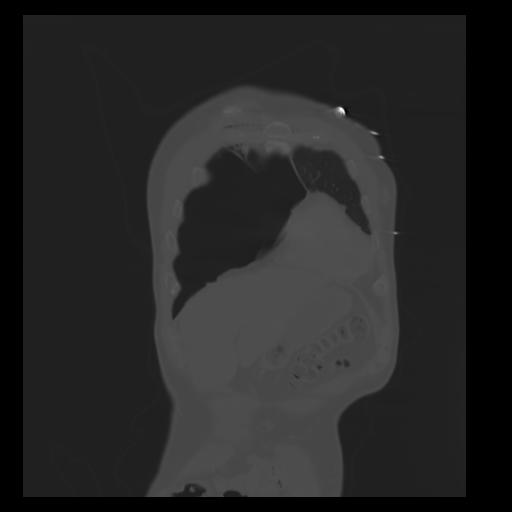

29 CUERPO,CE,Coronal,3.000,CUERPO,Coronal,